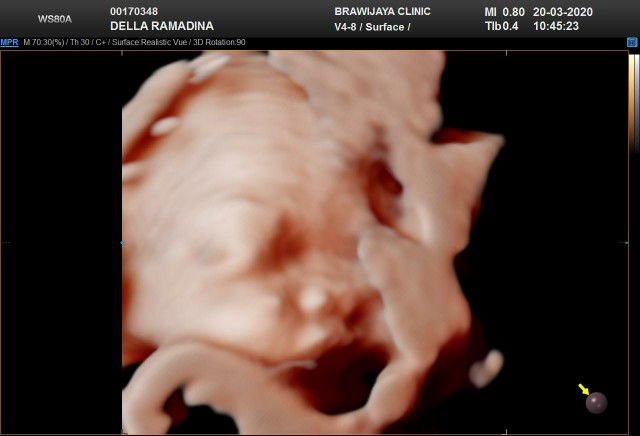

usg 4d

Bun.. disini ada yg udh usg di 24week?klo udah share dong fotonya dan pengalaman nya udah jelas apa belum ya.. soalnya aku rencana besok mau usg 4d pas di 24week?